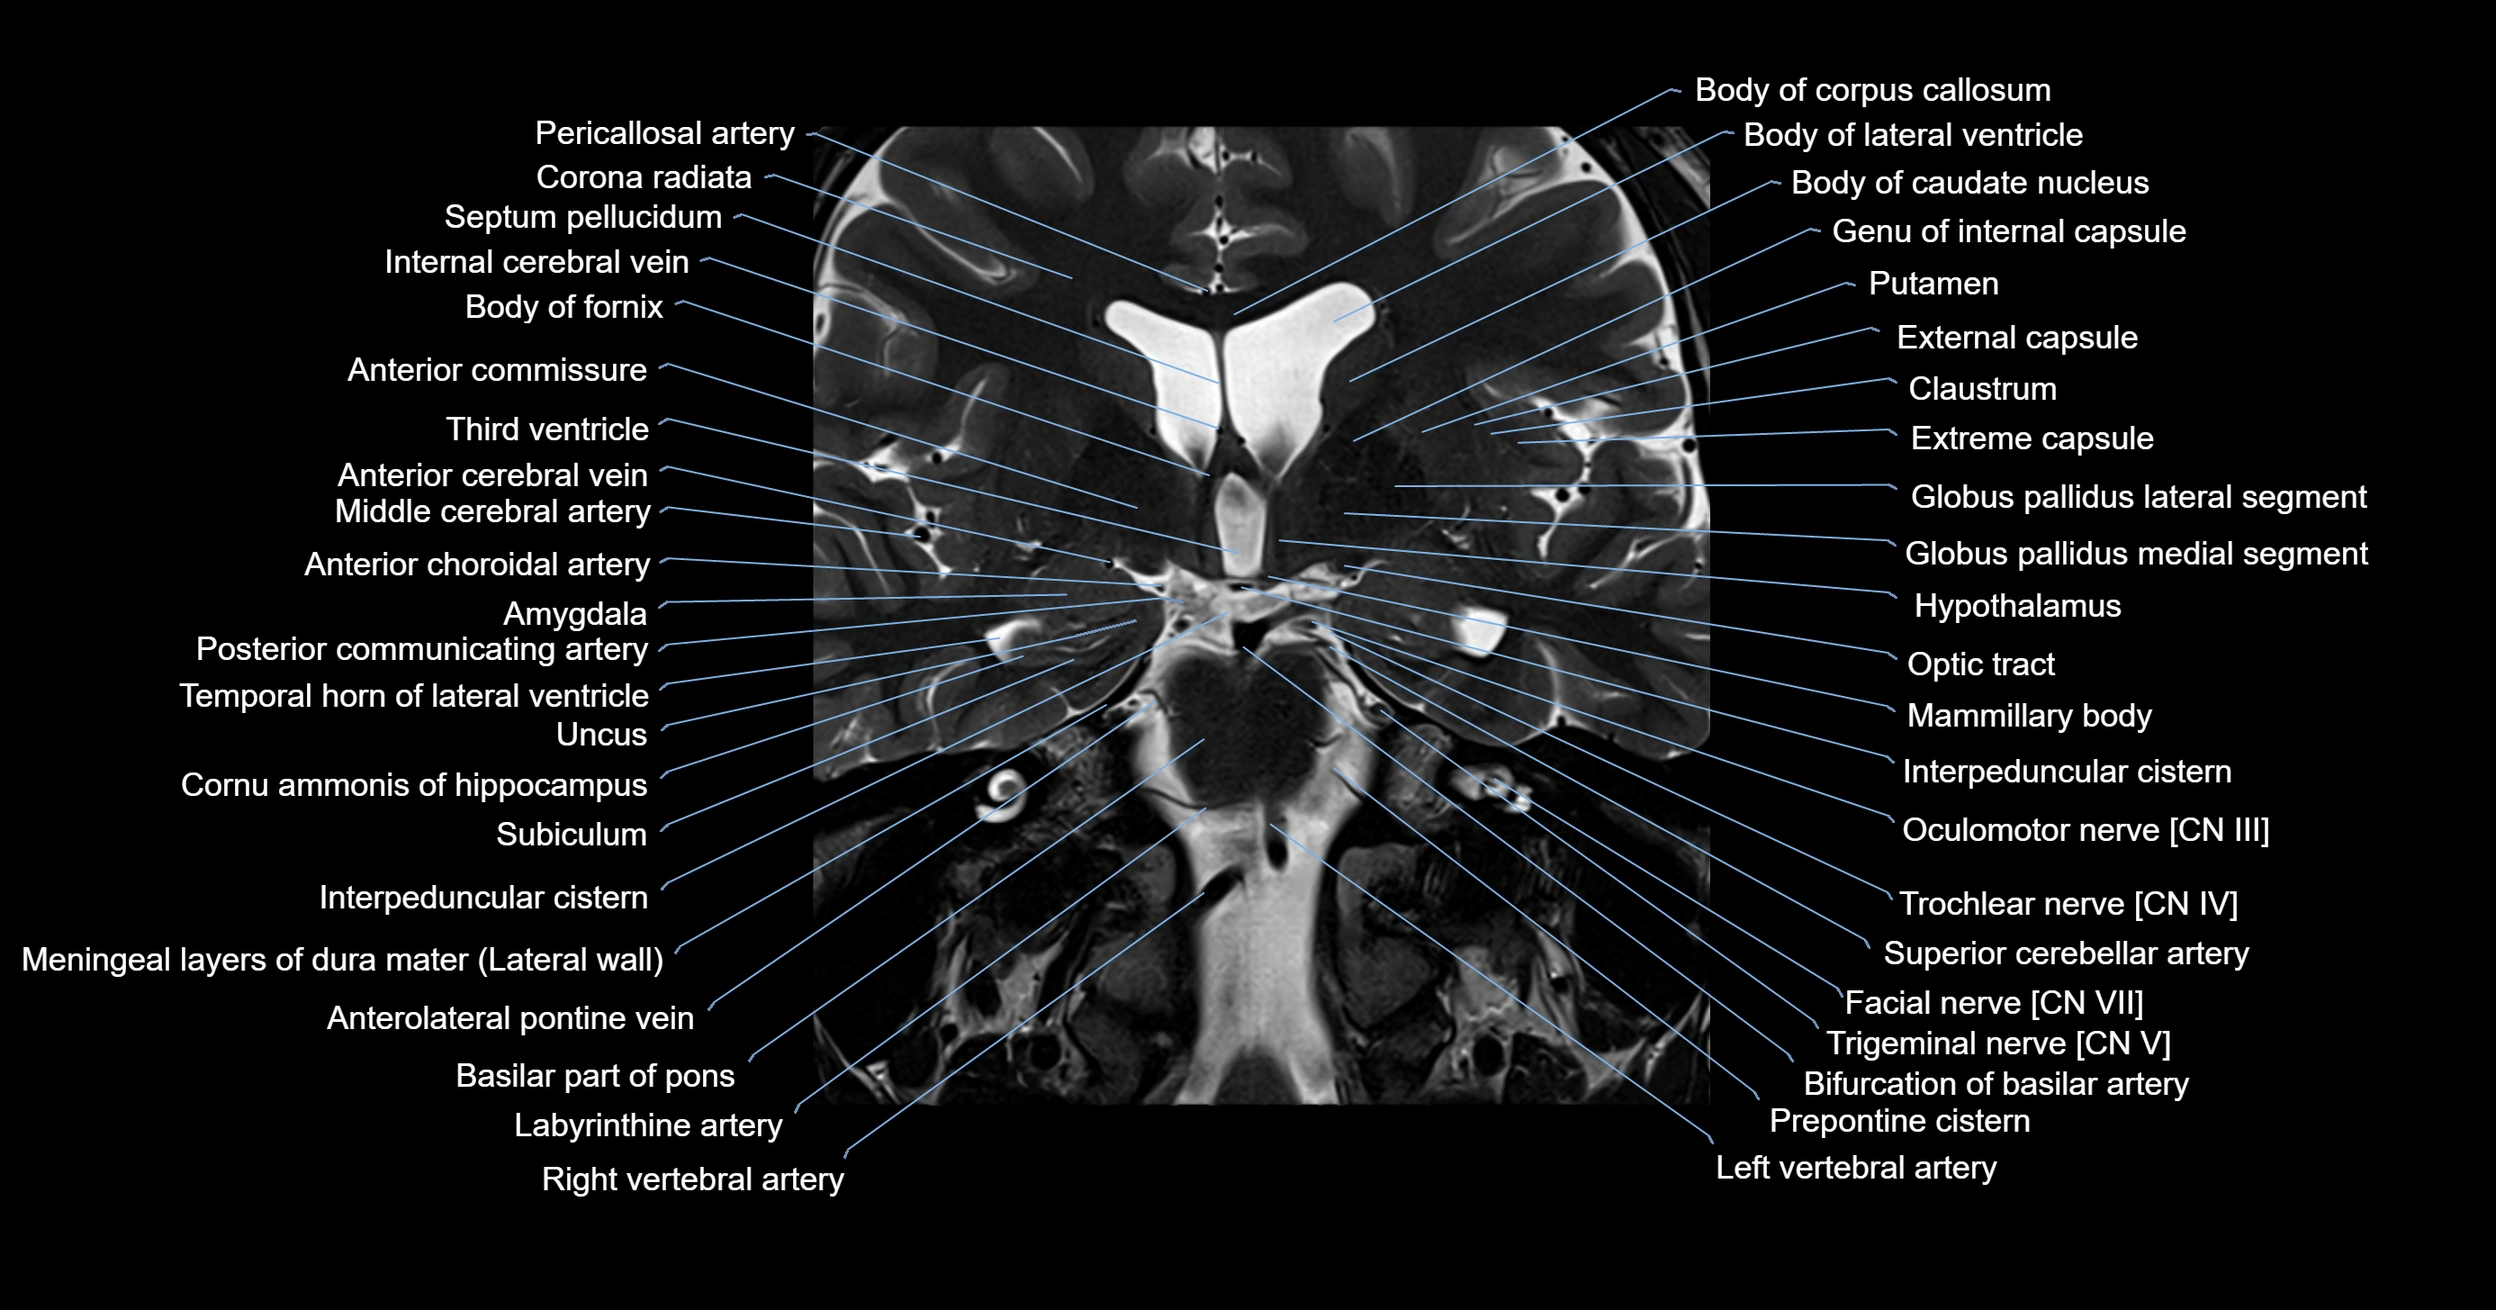

MRI images